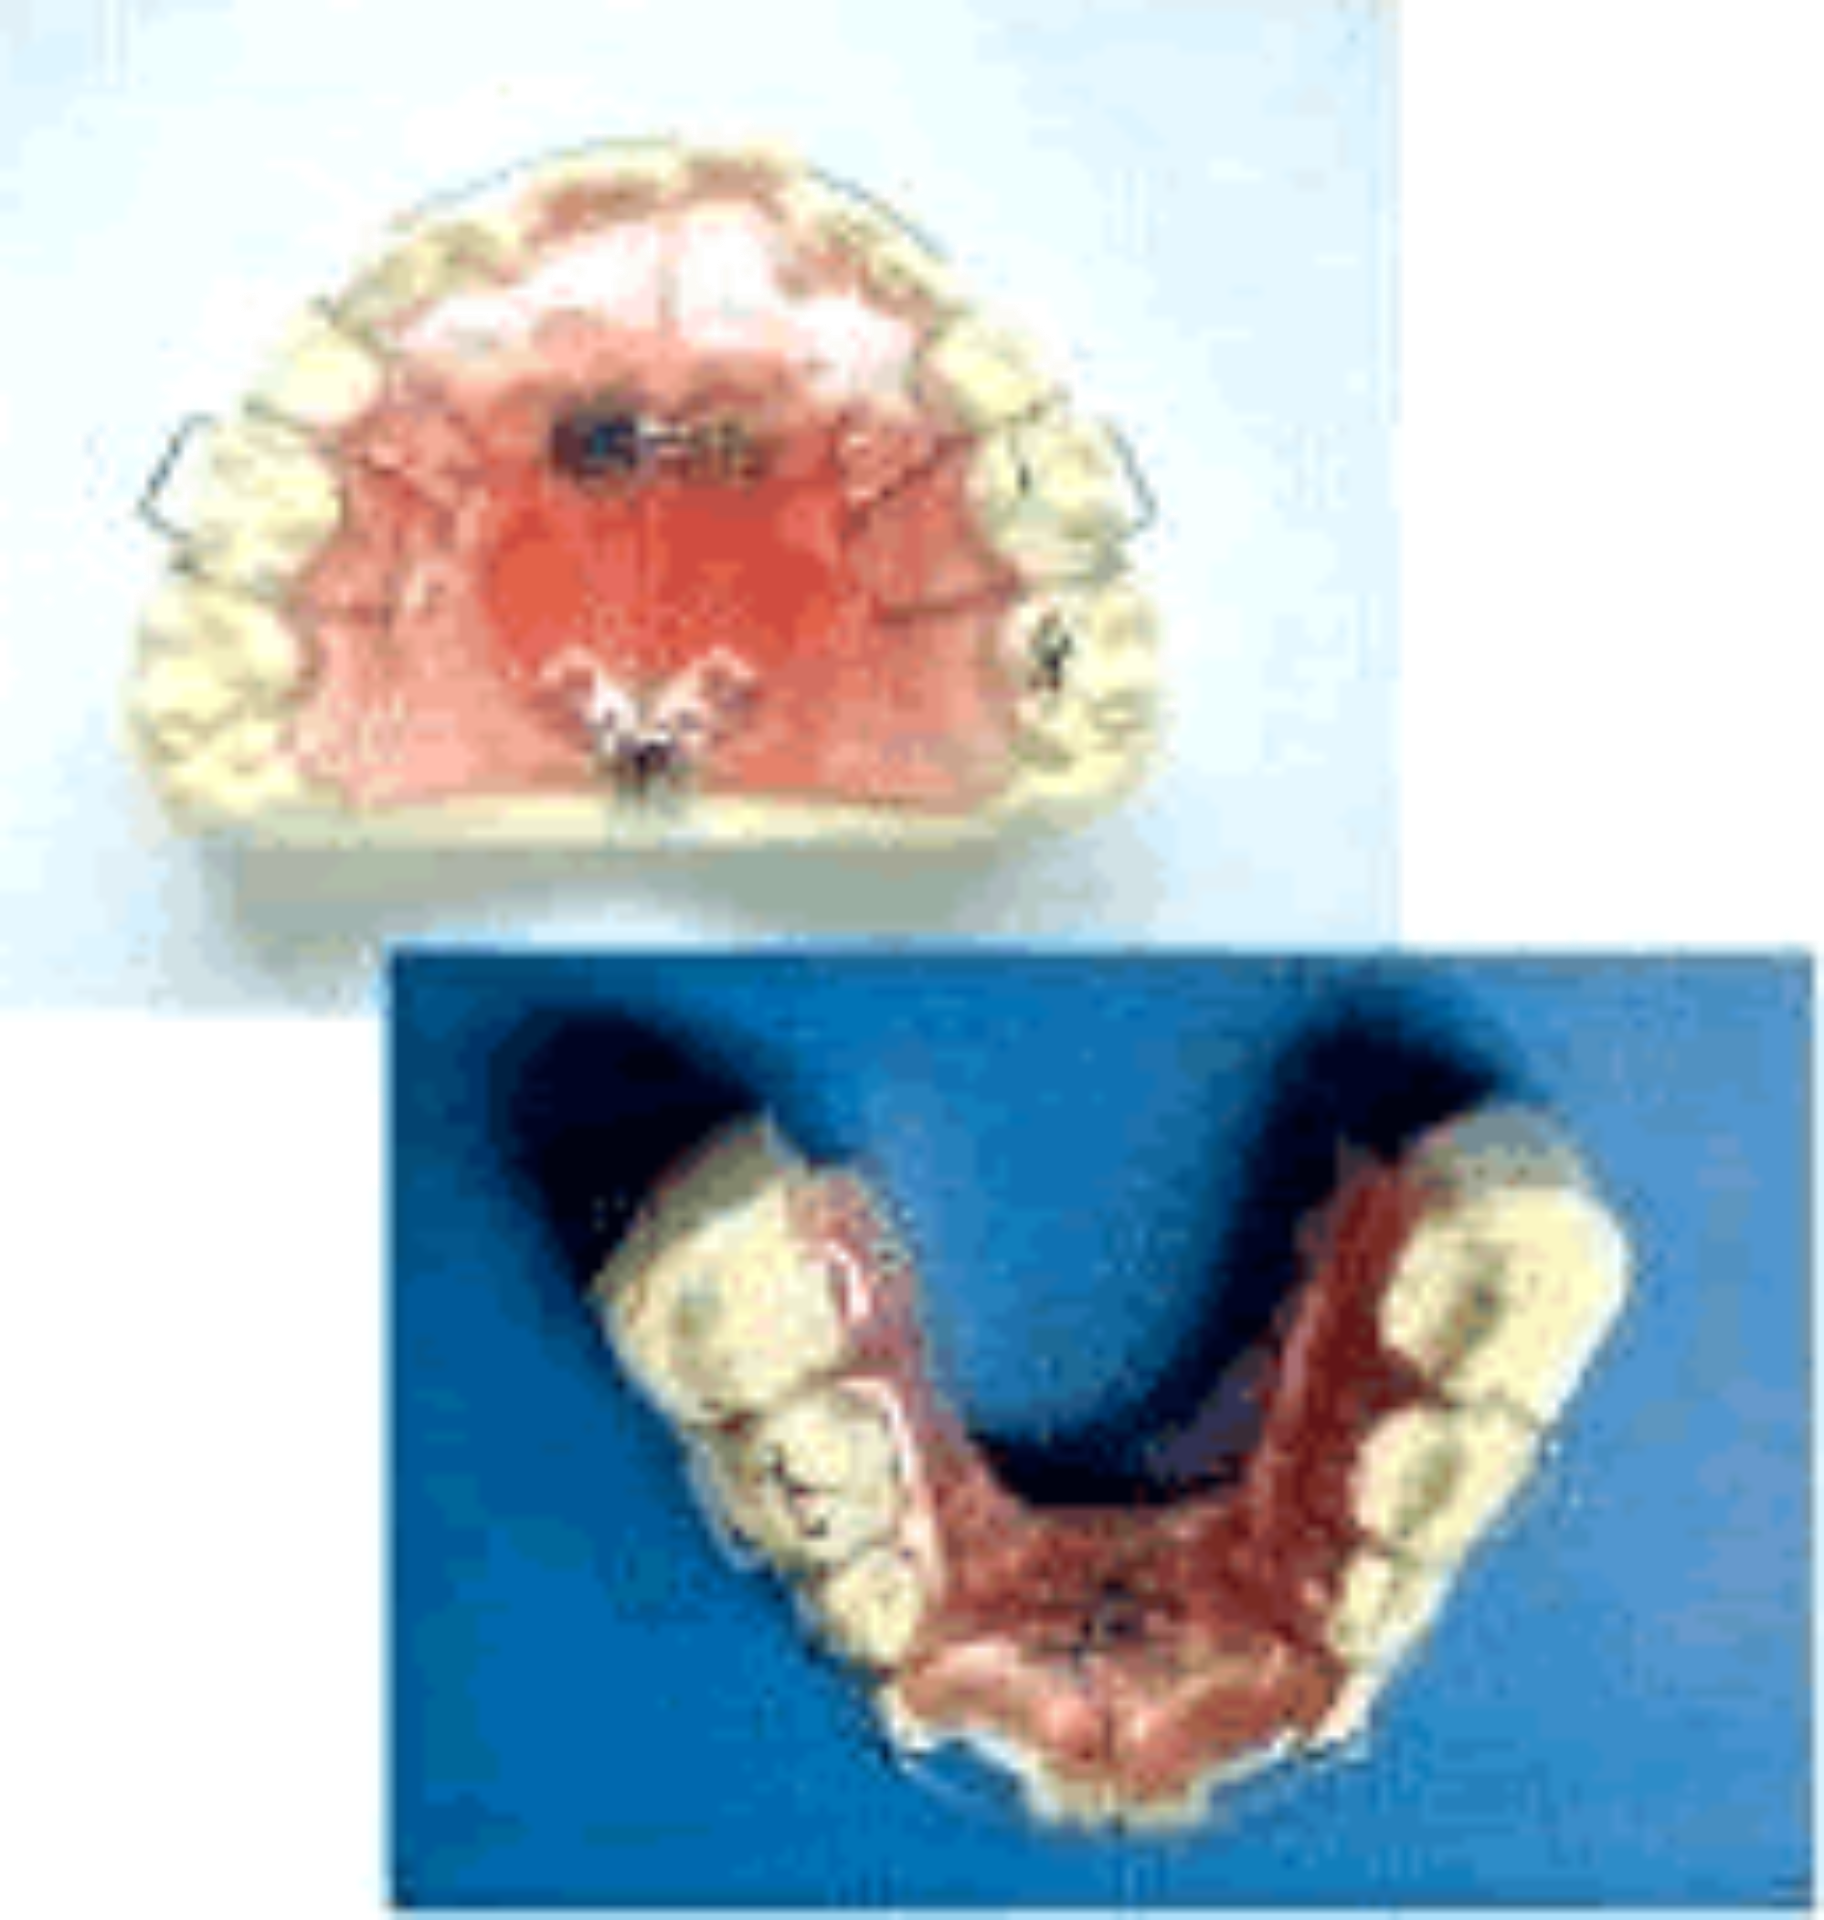

床矯正の治療では、基本的には永久歯を抜歯せずに、あご全体を広げて、歯のはえる場所を確保して、歯を並べます。

写真のようなネジ付き装置で少しづつ(1ヵ月約1㎜)顎を広げて、永久歯を正しい位置に誘導します。 写真のようなネジ付き装置で少しづつ(1ヵ月約1㎜)顎を広げて、永久歯を正しい位置に誘導します。その後、形状記憶合金のワイヤーを使うこともあります。 拡げる速さは自分で加減できます。 また、咬む運動、食事環境の指導、悪習慣の除去等を組み合わせ、歯の土台となる顎の骨の正常な発育を促すことにより、顔の形も整えます。 |

| ② ネジはいつ巻くのですか? 装置には、平行に拡がるタイプと扇状に拡がる2つのタイプがあります。 平行に拡がるタイプの装置は、ネジを90°回して0.2mm、 扇状に拡がる装置のタイプは、ネジを90°回して0.8mm拡大します。 歯を前方、後方に移動する場合は平行に拡がるタイプに準じます。 拡大は、1週間で90°ずつ1回ネジを巻くことを基本としています。 上顎の平行タイプでは、痛くなければ1ヶ月後から1日おきに45°ずつ、毎日拡大することもできます。 1週間で0.7mmの顎の拡大量がベストで、つまり、上顎は1ヶ月で約3mmの拡大が可能です。 下顎の歯肉は薄くできているため、下顎の拡大は、1週間で90°ずつ1回ネジを巻くことで1ヶ月で約1mmの拡大が基準です。 治療は適切に拡大ネジを回すことです。拡大しなければ、いつまでたっても治療は終了しません。 |